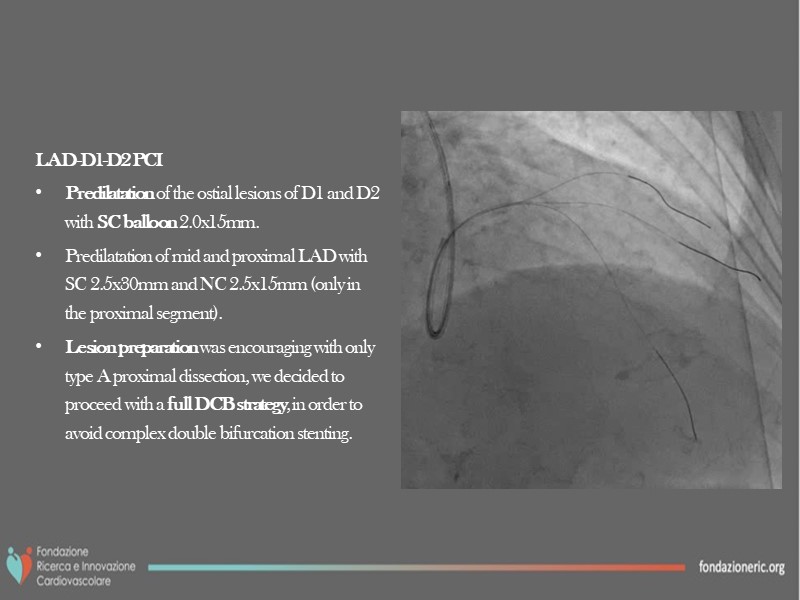

Thanks to the different interventions of this EuroPCR 2022 session, understand the role of paclitaxel DCB in modern era interventional cardiology, the differences, and advantages versus DES, the role of blended therapies in CLS, and learn how to correctly prepare the lesion and obtain the best from this technology on the long term.

- To learn how to correctly prepare the lesion and obtain the best from this technology on the long term